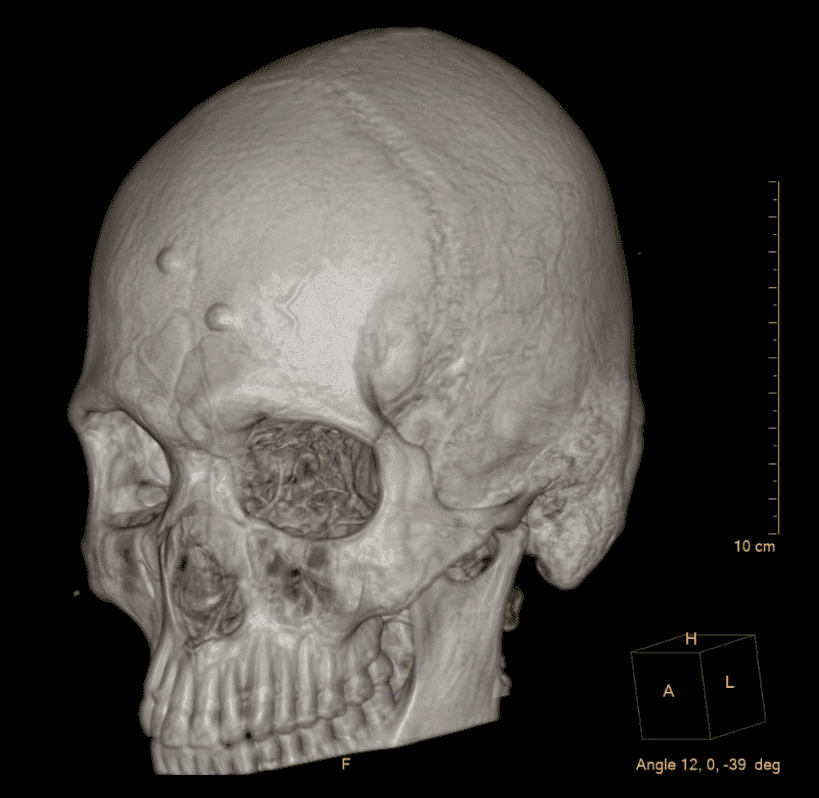

Visualización anatómica volumétrica para planeación quirúrgica.

Nuestra capacidad de realizar reconstrucciones tridimensionales permite a los médicos cirujanos planificar intervenciones con una precisión milimétrica, observando estructuras óseas y vasculares desde cualquier ángulo.